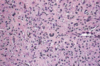

microscopic appearance of esoph squamou cell carcinoma

dysplastic/atypical squamous epithelium invading into submucosa or deeper

variably sized nests of tumor cells with epithelioid cells, ample eisinophilic cytoplasm, keratinization